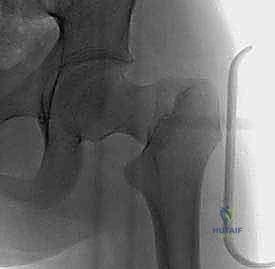

تصنيف ديلبيت (Delbet Classification) لكسور الورك

يستخدم أطباء العظام حول العالم، وعلى رأسهم الأستاذ الدكتور محمد هطيف، نظام "ديلبيت" لتصنيف كسور الورك عند الأطفال. هذا التصنيف ليس مجرد مسمى طبي، بل هو الدليل الأساسي الذي يحدد خطة العلاج ويتنبأ بنسبة حدوث المضاعفات.

| النوع الأول (Type I) | كسر عبر المشاشة (فصل رأس عظمة الفخذ عن عنق العظمة). | نادر جداً (أقل من 10%) | مرتفع جداً (تصل إلى 90%) | يتطلب تدخلاً جراحياً طارئاً وفورياً. |

| النوع الثاني (Type II) | كسر عبر عنق عظمة الفخذ (Transcervical). | الأكثر شيوعاً (حوالي 45%) | مرتفع (حوالي 50%) | رد مغلق أو مفتوح وتثبيت بمسامير. |

| النوع الثالث (Type III) | كسر قاعدي في عنق الفخذ (Cervicotrochanteric). | شائع (حوالي 30%) | متوسط (20% - 30%) | تثبيت جراحي داخلي محكم. |

| النوع الرابع (Type IV) | كسر بين المدورين (Intertrochanteric). | الأقل خطورة (حوالي 15%) | منخفض (أقل من 10%) | يمكن علاجه تحفظياً أحياناً، أو جراحياً. |

- الأشعة السينية (X-rays): صور أمامية وجانبية للحوض والورك لتأكيد الكسر وتحديد نوعه.